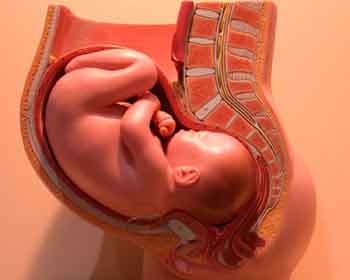

Fetus at 38 weeks after fertilization[4]

- ^ 3D Pregnancy (Image from gestational age of 40 weeks). Retrieved 2007-08-28. A rotatable 3D version of this photo is available here, and a sketch is available here.

![Fetus at 38 weeks after fertilization[4]](/w/images/3/31/40_weeks_pregnant.jpg)